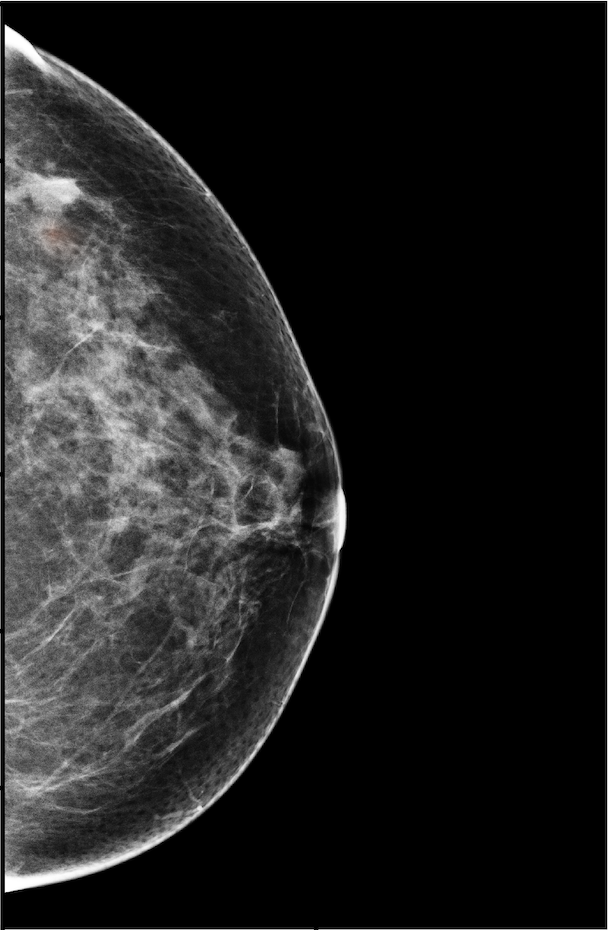

The NYU Breast Cancer Screening Dataset [78] includes 229,426 exams (1,001,093 images) from 141,472 patients.222Our retrospective study was approved by our institutional review board and was compliant with the Health Insurance Portability and Accountability Act. Informed consent was waived. Each exam contains at least four images which correspond to the four standard views used in screening mammography: R-CC (right craniocaudal), L-CC (left craniocaudal), R-MLO (right mediolateral oblique) and L-MLO (left mediolateral oblique). An example is shown in Figure 3.

Across the entire dataset (458,852 breasts), malignant findings were present in 985 breasts () and benign findings in 5,556 breasts (). All findings are confirmed by at least one biopsy performed within 120 days of the screening mammogram. For the remaining screening exams that were not matched with a biopsy, we assigned labels corresponding to the absence of malignant and benign findings in both breasts. In each exam, the two views of the same breast share the same label.

For all exams matched with biopsies, we asked a group of radiologists (provided with the corresponding pathology reports) to retrospectively indicate the location of the biopsied lesions. This way we obtained the segmentation labels: where if pixel belongs to the benign/malignant findings. An example of such a segmentation is shown in Figure 3. In all experiments (except for experiments in Section 3.6 that assess the benefits of utilizing segmentation labels), segmentation labels are only used for evaluation. We found that, according to the radiologists, approximately of exams were mammographically occult, i.e., the lesions that were biopsied were not visible on mammography, even retrospectively, and were identified using other imaging modalities: ultrasound or MRI.